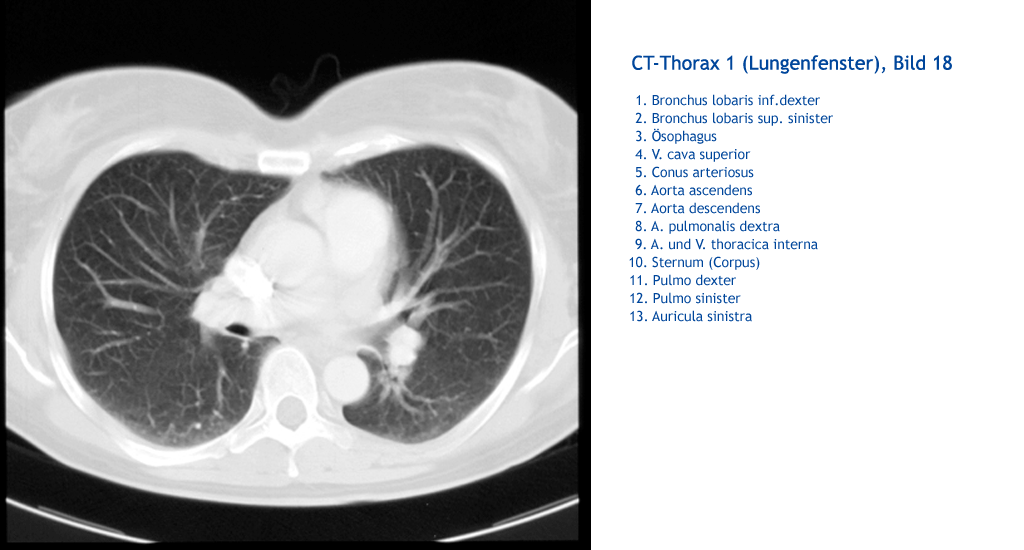

Auricula sinistra Pulmo sinister Pulmo dexter Sternum (Corpus) A. und V. thoracica interna A. pulmonalis dextra Aorta descendens Aorta ascendens Conus arteriosus V. cava superior Ösophagus Bronchus lobaris sup. sinister Bronchus lobaris inf. dexter